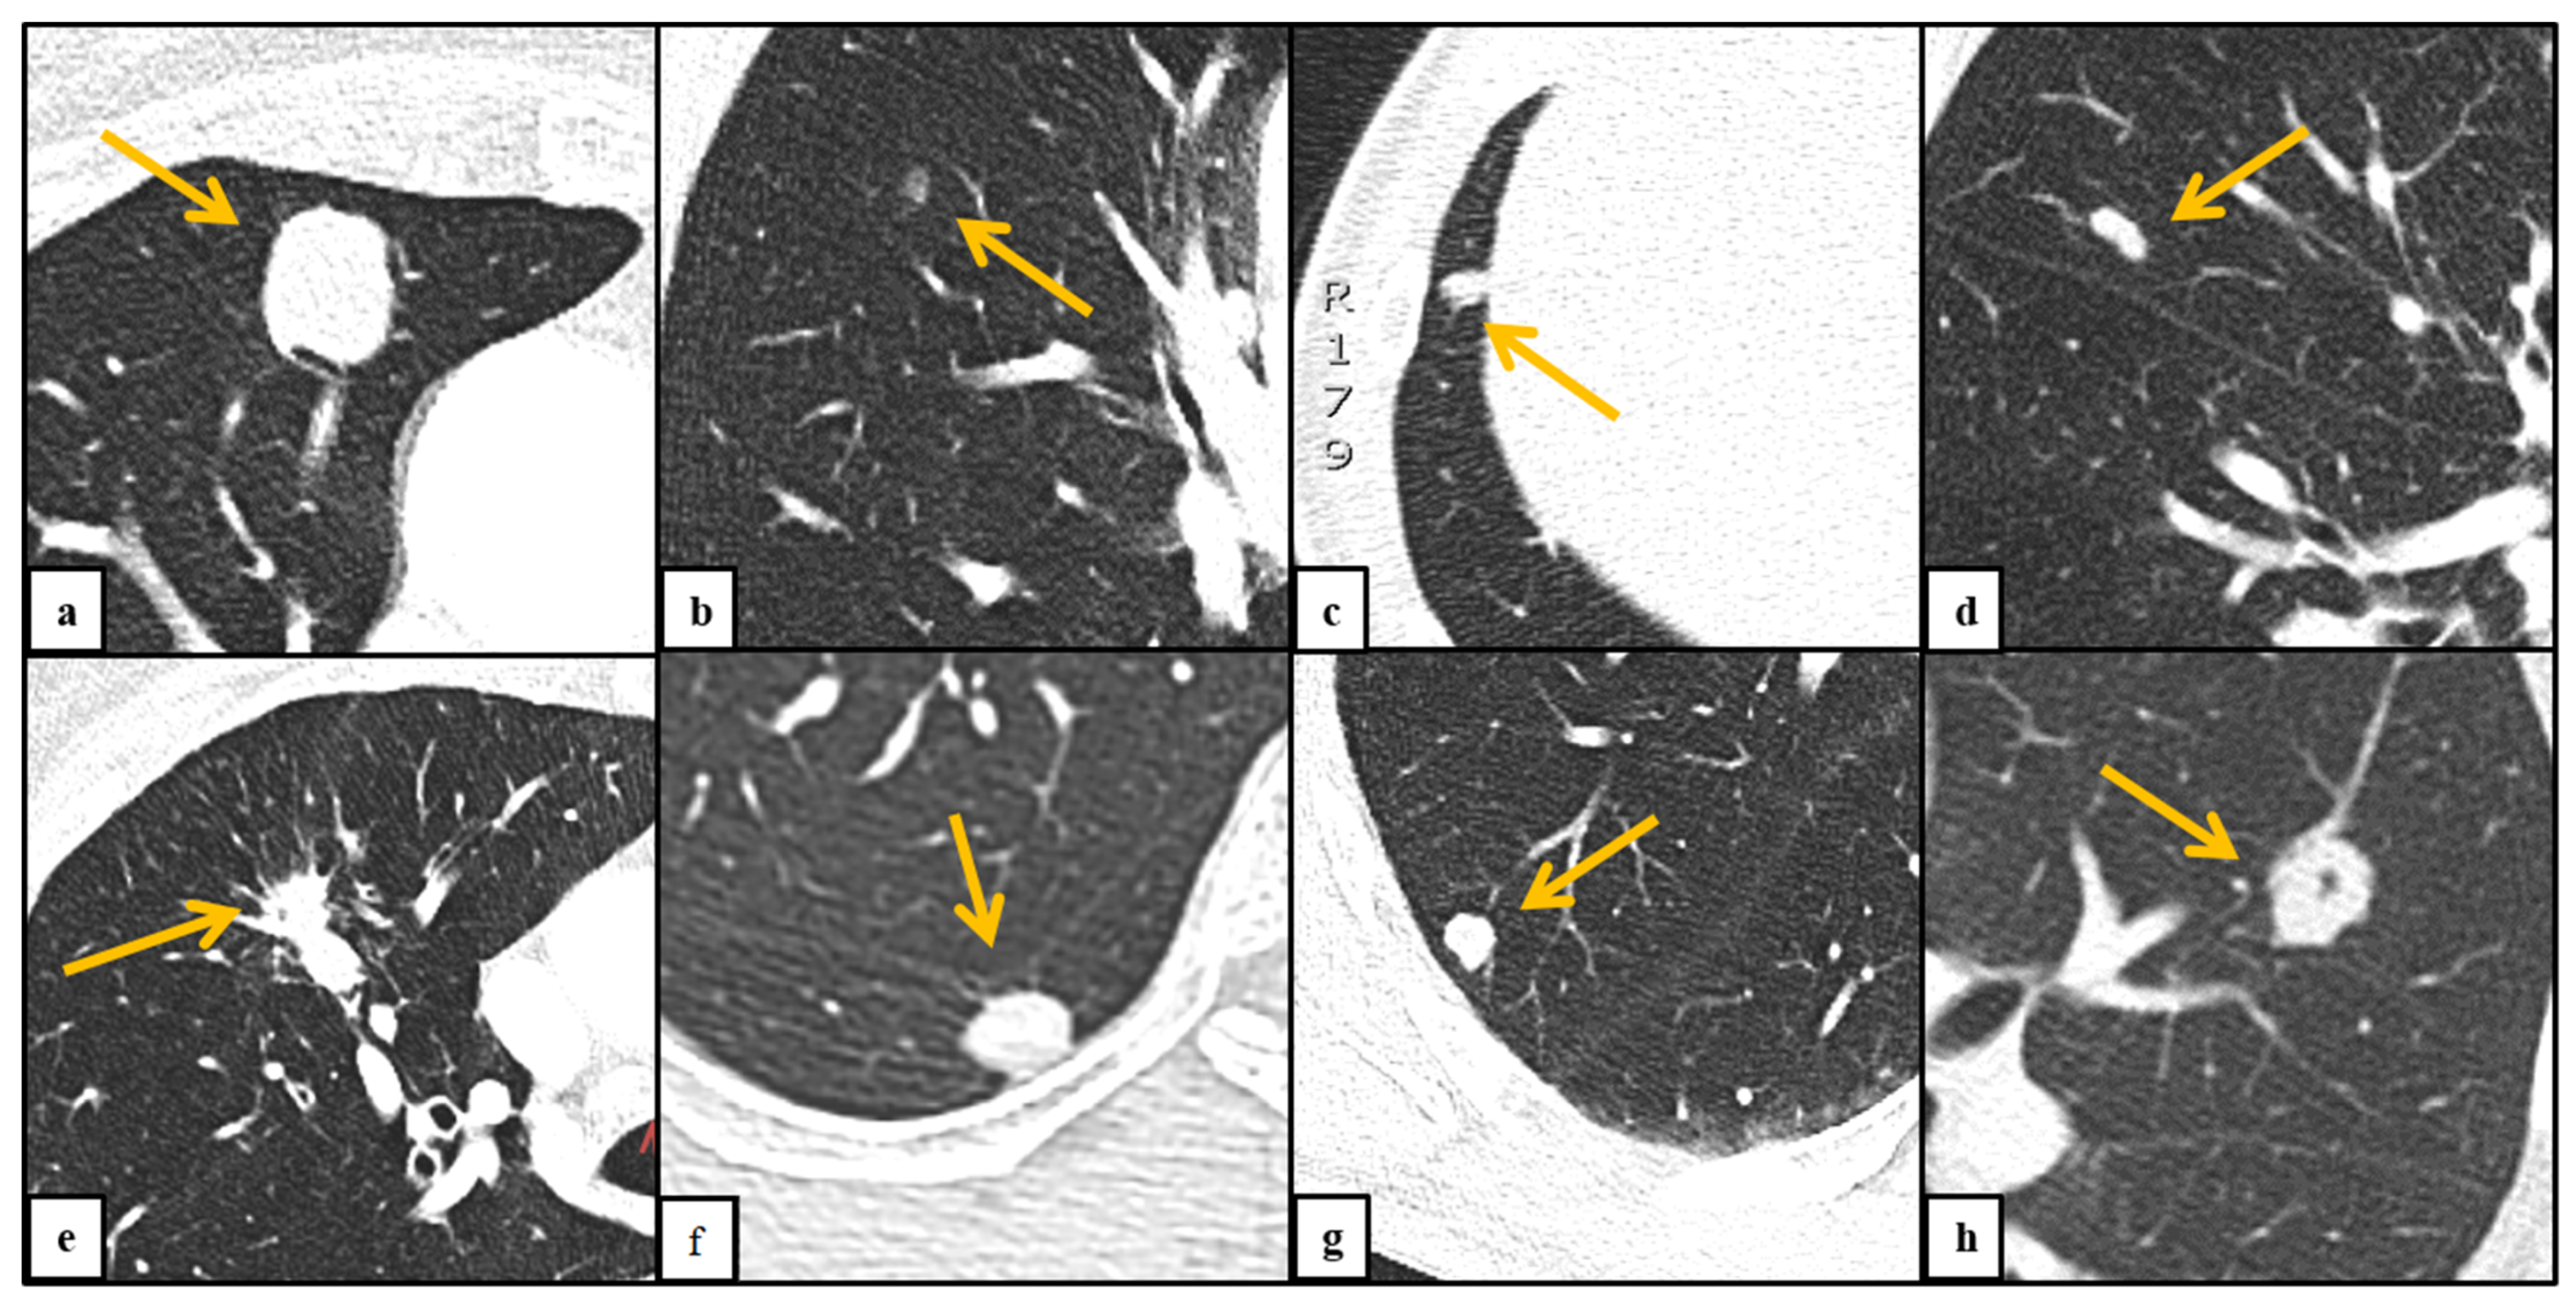

| Morphology | |||||||

| Subsolid | 53 | 12% | 29 | 20% | 24 | 8% | <0.001 |

| Non-solid | 8 | 2% | 7 | 5% | 1 | 0.3% | |

| Part-solid | 45 | 10% | 22 | 15% | 23 | 8% | |

| Solid | 385 | 88% | 113 | 80% | 272 | 92% | |

| Margin | |||||||

| Ill-defined | 24 | 6% | 7 | 6% | 17 | 6% | 0.821 |

| Well-defined | 387 | 88% | 129 | 91% | 258 | 87% | |

| Lobulated | 22 | 5% | 5 | 4% | 17 | 26% | |

| Spiculated | 5 | 1% | 1 | 1% | 4 | 1% | |

| Pleura retraction | |||||||

| No | 431 | 98% | 142 | 100% | 289 | 98% | 0.102 |

| Yes | 7 | 2% | 0 | 0% | 7 | 2% | |

| Feeding Vessel | |||||||

| No | 214 | 49% | 76 | 54% | 138 | 47% | 0.186 |

| Yes | 224 | 51% | 66 | 46% | 158 | 53% | |

| Calcification | |||||||

| No | 425 | 97.0% | 129 | 91% | 296 | 100% | <0.001 |

| Yes | 13 | 3.0% | 13 | 9% | 0 | 0% | |